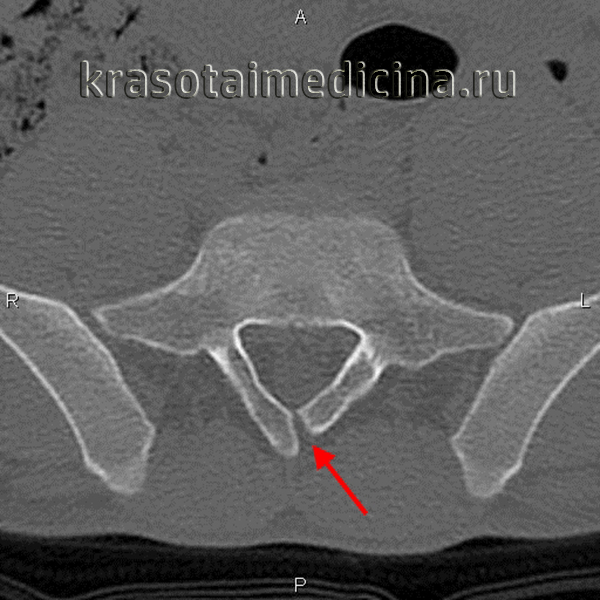

3. КТ признаки неполного слияния позвонка (spina bifida occulta):

• Костная КТ:

о Незаращение остистого отроака/плааинки дуги

(Справа) На аксиальном Т1-ВИ видно типичное неполное слияние задних элементов позвонка по срединной линии. Эта находка стала случайной в ходе проведения обследования пациента по поводу болевого синдрома в нижней части спины. (Слева) КТ, фронтальный срез: признаки косого асимметричного расположения пластинок дуги L5 позвонка, наслаивающихся друг на друга, — та -кая конфигурация приводит к ротационной перегрузке дугоотростчатых суставов и преждевременной их дегенерации.

(Справа) КТ, аксиальный срез на уровне пояснично-крестцового перехода: у пациента с косым расположением ротацией и неполным слиянием задних элементов позвонка дополнительно выявлен дефект межсуставной части дуги L5 (без дислокации), возникший, возможно, на фоне ротационной перегрузки межсуставной части дуги.